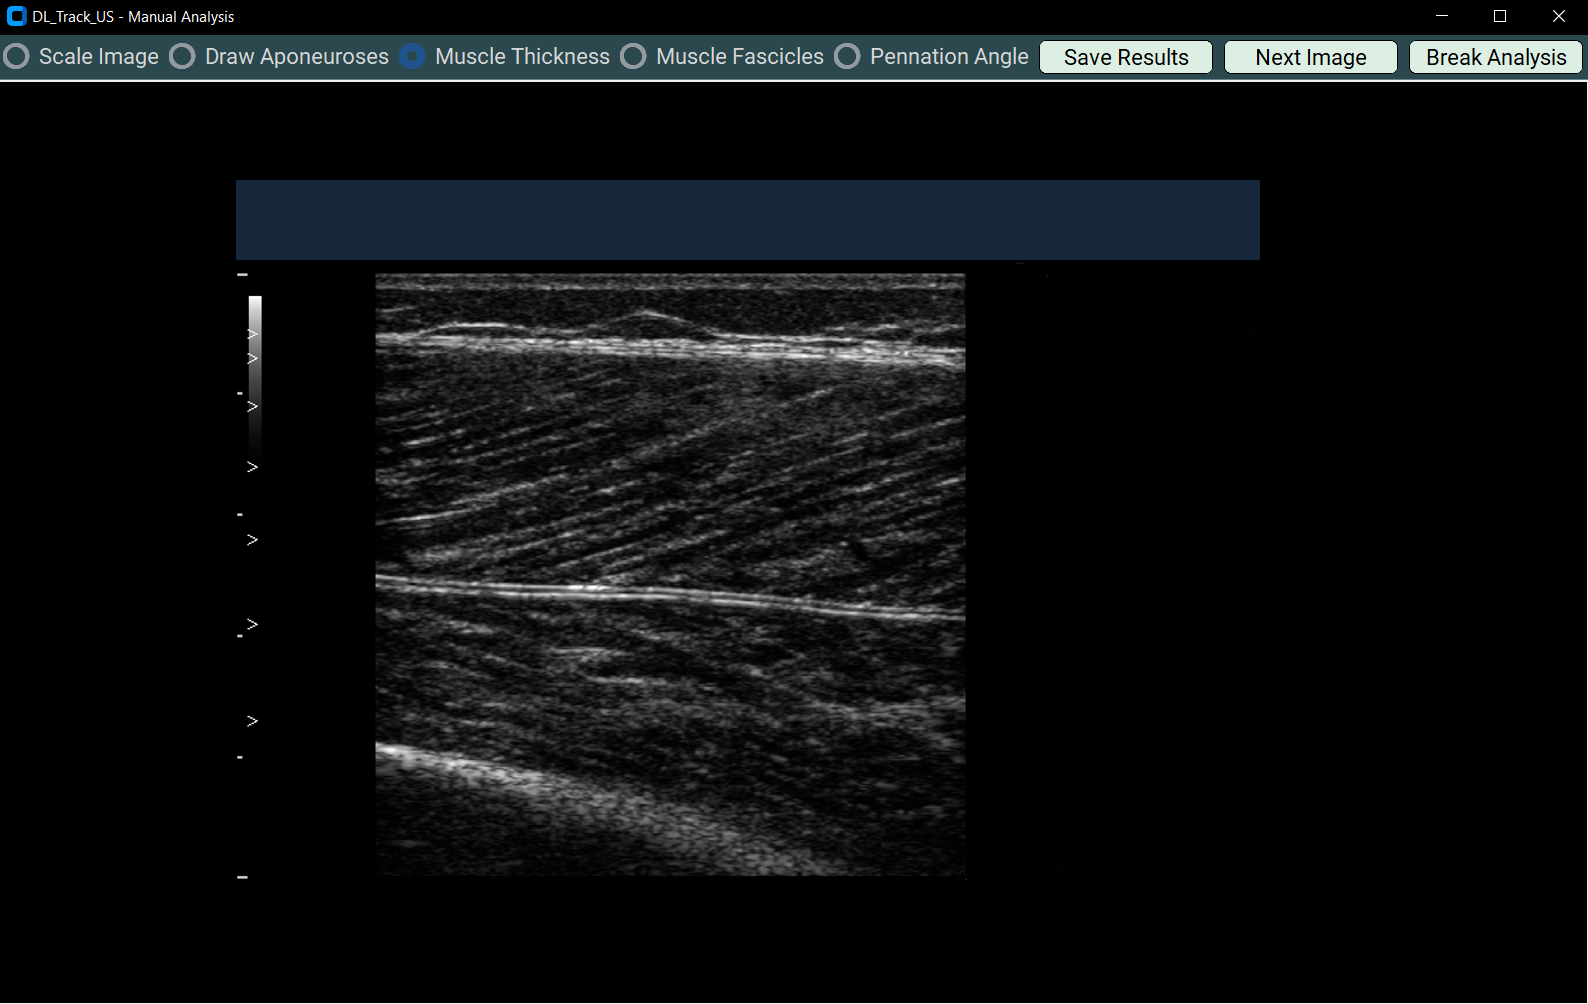

4.3 Measuring Muscle Thickness¶

- Select Muscle Thickness.

- Draw three straight lines from superficial to deep aponeurosis across the muscle image.